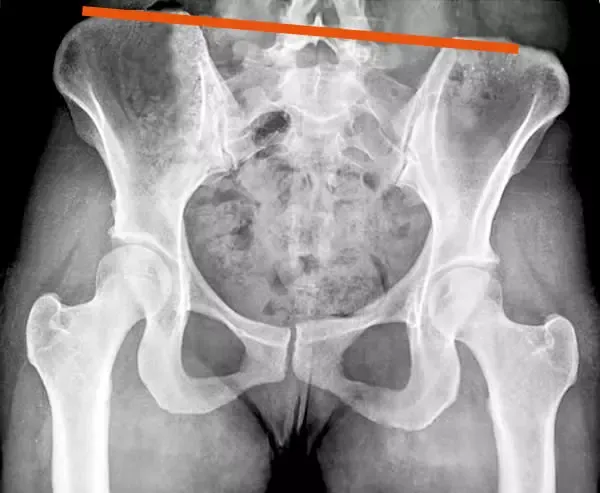

Terapijo za zdravljenje različnih poškodb oziroma težav določimo individualno, zato na obisk pri fizioterapevtu s seboj prinesite tudi svoje izvide. Tako bomo lahko natančno izdelali potek zdravljenja in po končani fizioterapiji s ponovnim pregledom oziroma kontrolo pri vašem zdravniku potrdili uspešnost.